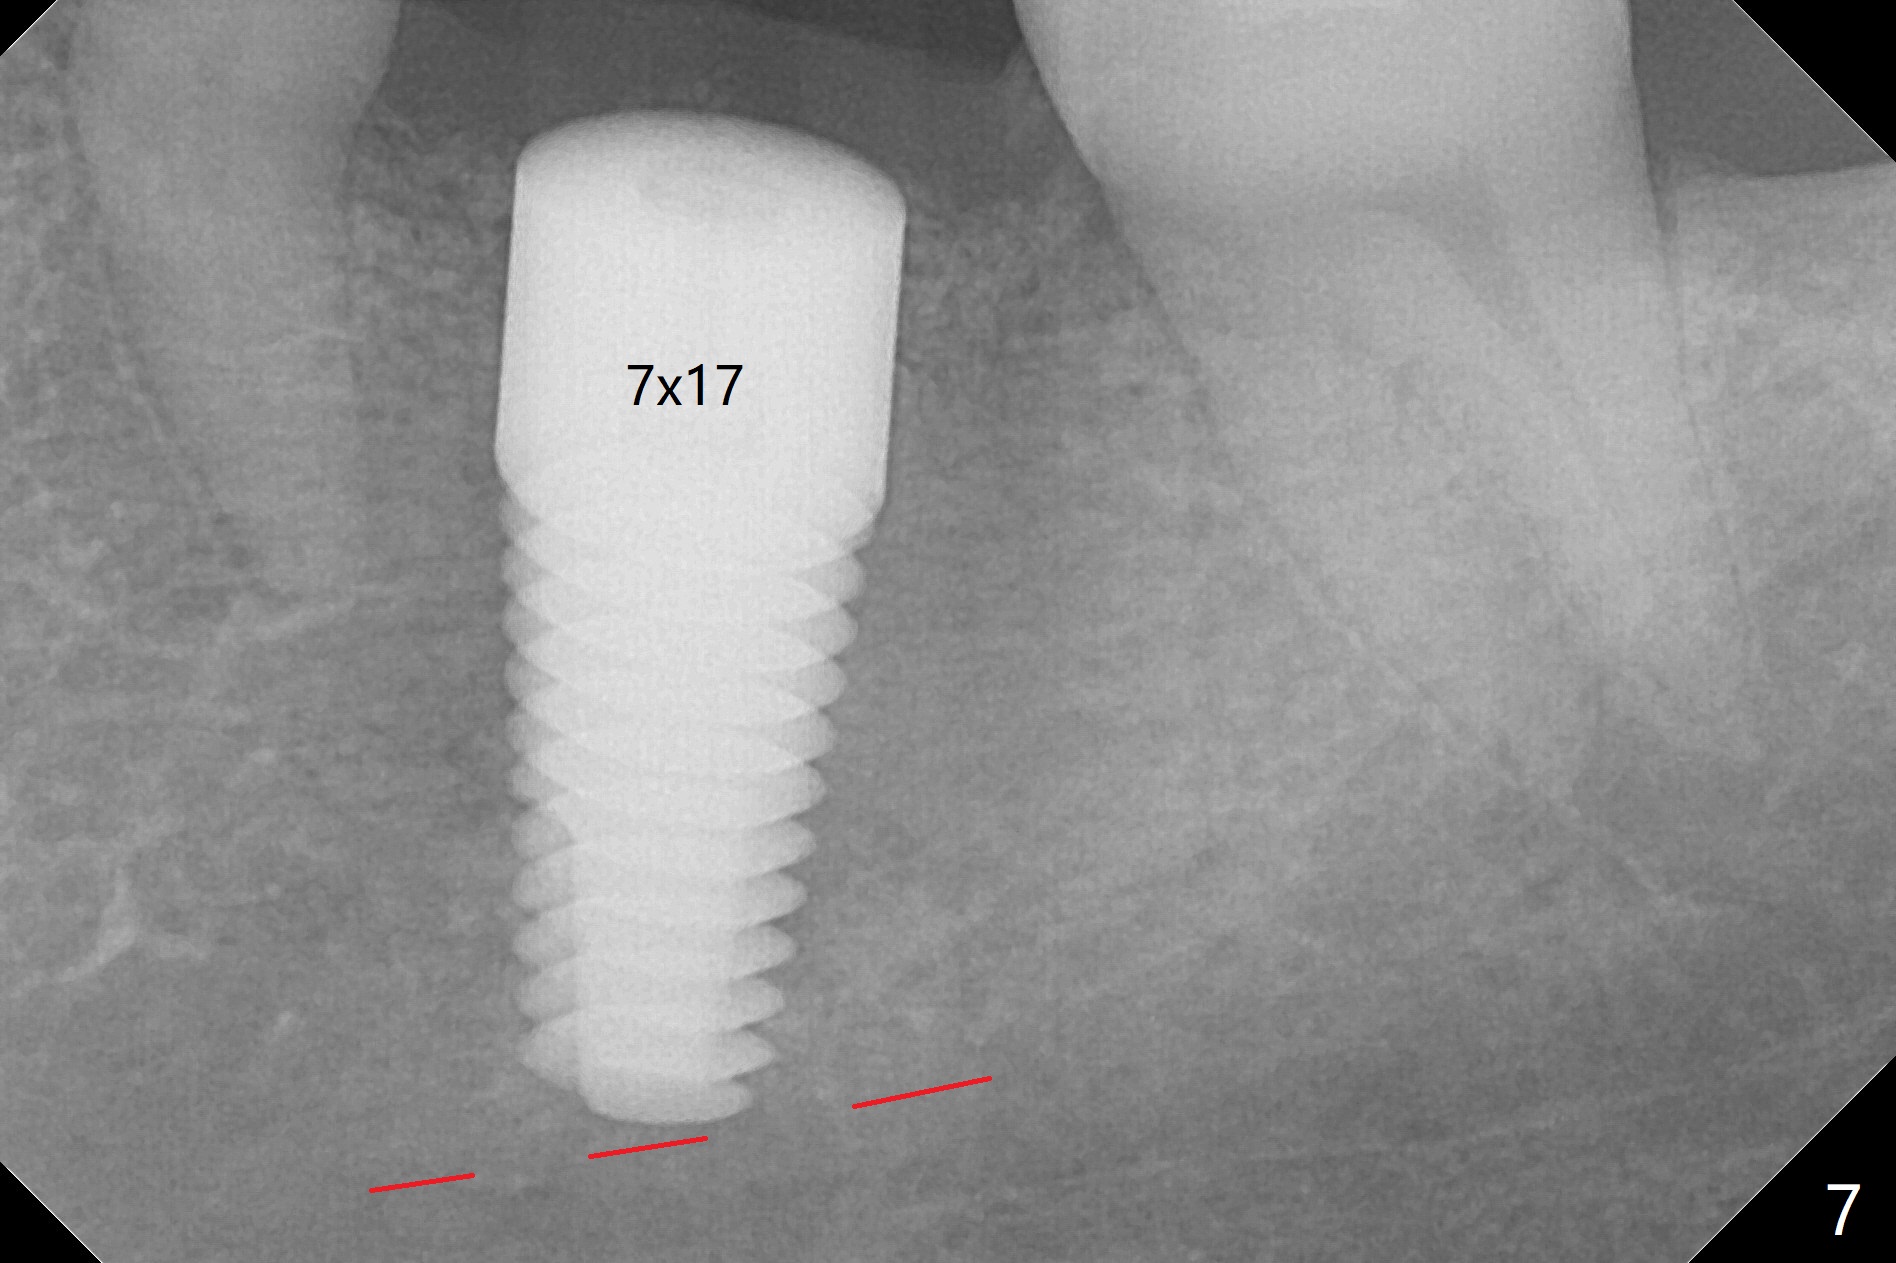

After 4.0x10 mm drill with 9 mm offset for 4.5x10 mm bone-level implant at #19, a 4.5x17 mm tissue level tap is inserted with apparently low torque (probably without reaching the depth). When a 4.5x14 mm tissue level implant is placed with high torque, a 4.5x7.3 mm drill is used for ~ 6.5 mm. The implant loses the primary stability with over-insertion (Fig.1). When an abutment is placed, the implant is critically loose. Mixture of autogenous bone, Osteogen and allograft is placed in the osteotomy. The implant regains stability with better placement level for restoration (Fig.2). In fact the bone density around the implant increases (Fig.2 *). For the first 7 days postop, the patient has to take Advil. When he returns for follow up 8 days postop (Fig.3), the pain decreases, while there is minor degree of lower lip paresthesia. Medrol Dose Pak and Tylenol III are prescribed. The implant is loose 24 days postop; after removal of the implant and apparently infected bone graft, a 7x14 mm dummy implant is inserted with <20 Ncm and 3-4 mm clearance (Fig.4). A longer dummy implant seems to improve stability (Fig.5). So does the definitive implant (Fig.6,7, 25 Ncm), but it is placed low. The gingiva looks healthy 13 days postop (2nd placement). A healing cap will be placed for restoration ~ 3 months postop. CT will be taken if the implant needs to be backed up to determine whether there is enough bone buccolingually. Due to coronavirus and prolonged placement of a healing abutment with poor oral hygiene, the buccal gingiva of the implant is erythematous 1 year postop (Fig.8 healing cap just removed) with bone loss (Fig.9,10 *). Sticky bone seems to be necessary. A 6x5 mm abutment with slots will be placed to hold periodontal dressing in place.